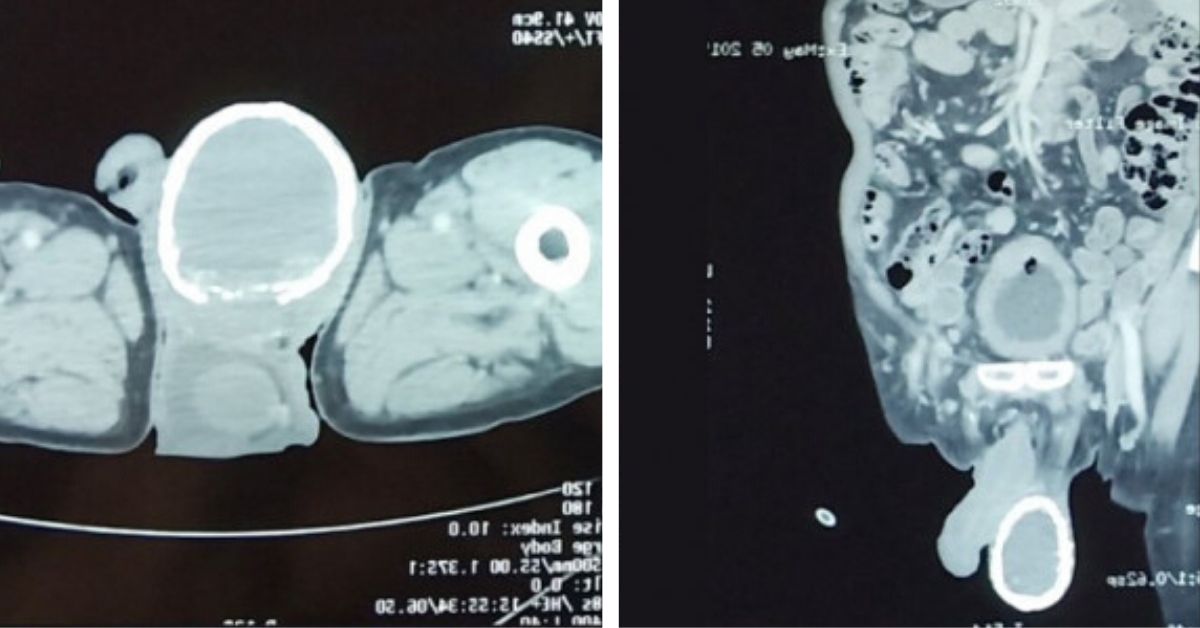

Left testicle ultrasound showing enlarged testicle with areas of

Left testicle ultrasound showing enlarged testicle with areas of What Is Enlarged Testicle Scrotal swelling is an enlargement of the scrotal sac, or scrotum, which houses the testicles. An enlarged testicle occurs when the testicle or surrounding structure swells. When to see a doctor. It occurs when the scrotum (the sac surrounding the testicles) grows abnormally large. It may be due to an injury, infection, or, in rare cases, cancer. It can be. What Is Enlarged Testicle.